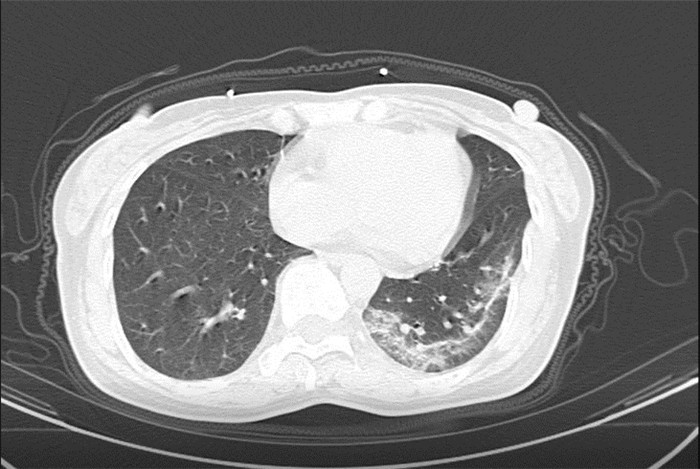

武漢大學(xué)中南醫(yī)院影像科副主任張笑春教授發(fā)現(xiàn),目前武漢市家庭聚集性發(fā)病較多,而且大多起病隱匿,一次甚至多次核酸陰性,無(wú)任何臨床癥狀,CT檢查卻已顯示為病毒性肺炎特征。

為了盡快篩查新型冠狀病毒肺炎患者,醫(yī)院會(huì)選擇影像診斷作為早期發(fā)現(xiàn)新型冠狀病毒感染的肺炎的重要一環(huán)。

CT為當(dāng)前首選篩查與診斷的主要影像學(xué)手段,胸部CT的病毒性肺炎檢出率高。